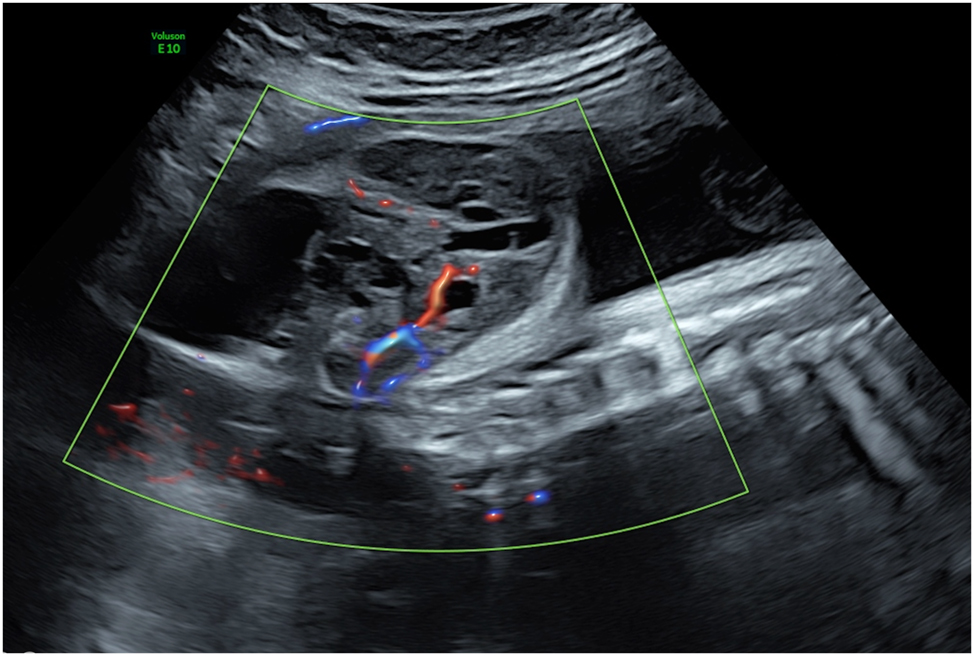

Bronchopulmonary sequestration

When an abnormal solid lung region, disconnected from the bronchial system, is supplied by a systemic arterial vessel, typically arising from the thoracoabdominal aorta, it is referred to as bronchopulmonary sequestration (BPS) [71] (Figure 9A). The natural history is variable. A large single-center study reported that approximately 70 % of fetuses with BPS did not develop hydrops, allowing for conservative management with favorable outcomes [72]. However, particularly with large lesions, there is a risk of hydrops. A possible cause for hydrops development under discussion is mediastinal shift, leading to compression of the systemic veins, increased central venous pressure, reduced cardiac output, and the subsequent development of hydrops [73]. In severe cases, this can result in intrauterine death if intervention is not undertaken.

Figure 9:

Ultrasound images depicting bronchopulmonary sequestration and its management. (A) Transverse thoracic view showing bronchopulmonary sequestration with aortic perfusion and fetal hydrops. (B) Intrafetal laser coagulation of the feeding vessel using a laser fiber inserted through an 18-gauge needle under ultrasound guidance. Courtesy of Prof. Dr. Ingo Gottschalk.

Emerging evidence suggests that laser ablation of the feeding vessel is the most effective therapy BPS complicated by hydrops. This procedure involves using interstitial laser to occlude the systemic arterial vessel supplying the sequestered lung tissue [10], [11], [12, 72], 74]. Historically, alternative approaches included thoraco-amniotic shunt placement or serial thoracocentesis for associated pleural effusions [72], 75], 76]. However, the limited studies available to date indicate that interstitial laser therapy is more effective and carries lower risks compared to shunt insertion [10], 72].

The laser procedure is performed as an intrafetal intervention, similar to the technique used in TRAP sequence. Following local anesthesia, an 18-gauge needle is guided under ultrasound visualization to the feeding vessel of the sequestration, where laser energy is applied to coagulate the vessel (Figure 9B) [10], 72], 77]. Critical to procedural success is avoiding puncture of other fetal organs, including healthy lung tissue, and applying only short laser pulses to prevent collateral damage. Gottschalk and colleagues reported that approximately 42 % of cases required a second intervention [11], highlighting the technical challenges of achieving complete vascular occlusion in a single procedure.